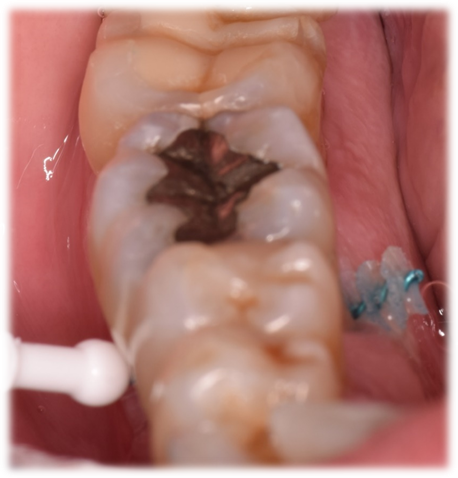

Los cepillos interdentales deben de ser insertados suavemente para no lesionar los tejidos en el proceso de cepillado y que el mismo pueda ser eficaz por más tiempo. La inserción comienza en el espacio interdental por vestibular con movimientos circulares hasta que alcance el otro lado lingual o palatino y ahí hacer movimientos horizontales. Siempre se debe enjuagar el cepillo entre un espacio interdental y otro. En áreas posteriores donde los tejidos vestibulares y palatinos/linguales están en diferentes niveles, el mismo se puede curvar sutilmente para que su punta no impacte con el tejido del lado opuesto, resultando en una lesión accidental de los tejidos blandos (Figuras 4 y 5).

Fig. 6: B- Uso de cepillo interdental en zona inter-radicular de molar inferior, luego de un procedimiento de tunelización para tratamiento de furca grado 2.